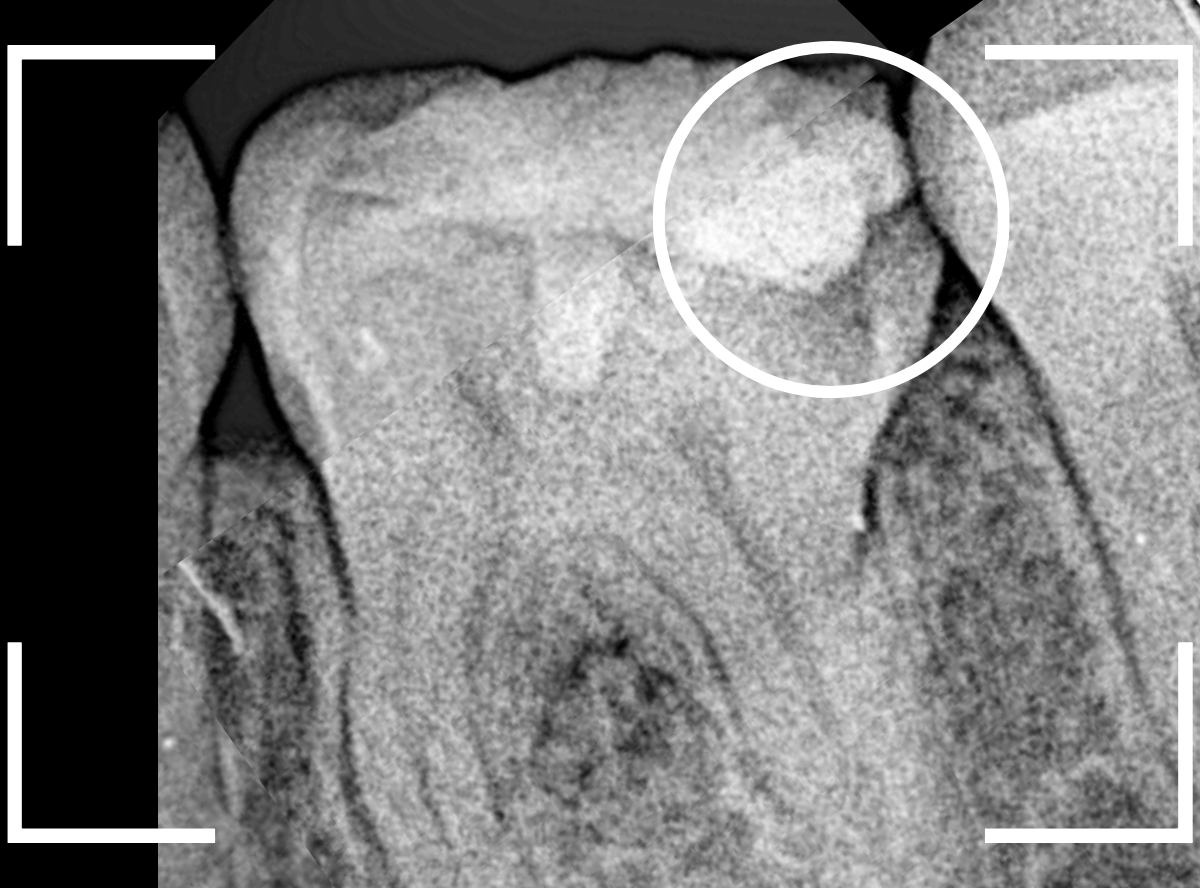

レントゲン写真で確認します。

青い線が神経、赤い線が虫歯です。

神経に触ってしまいそうなほどの大きな虫歯です。

(隣の歯も虫歯がありそうです)